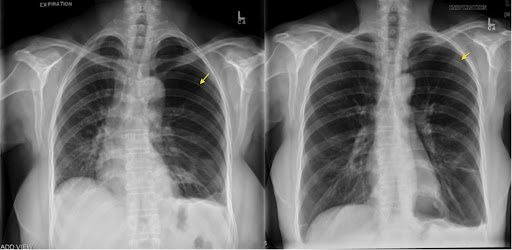

En cas de suspicion de pneumothorax, le médecin peut recourir à une radiographie thoracique ou à un scanner (tomodensitométrie) pour diagnostiquer le pneumothorax et obtenir des images détaillées des poumons.

Un pneumothorax se caractérise par la présence d’air autour ou à l’extérieur du poumon, dans l’espace pleural ou au niveau de la plèvre pariétale et viscérale à l’intérieur de la cage thoracique. L’air peut s’accumuler dans l’espace pleural et entraîner un affaissement partiel ou complet des poumons. Le pneumothorax est également appelé « poumon affaissé » ou « poumon perforé ».